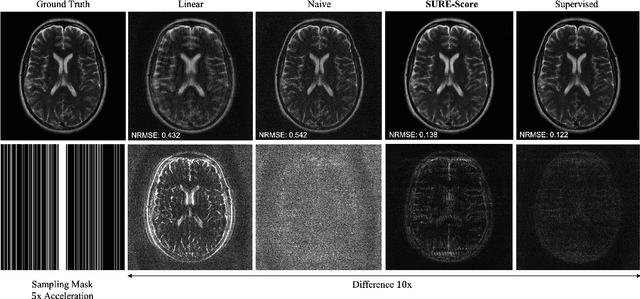

Abstract:We present SURE-Score: an approach for learning score-based generative models using training samples corrupted by additive Gaussian noise. When a large training set of clean samples is available, solving inverse problems via score-based (diffusion) generative models trained on the underlying fully-sampled data distribution has recently been shown to outperform end-to-end supervised deep learning. In practice, such a large collection of training data may be prohibitively expensive to acquire in the first place. In this work, we present an approach for approximately learning a score-based generative model of the clean distribution, from noisy training data. We formulate and justify a novel loss function that leverages Stein's unbiased risk estimate to jointly denoise the data and learn the score function via denoising score matching, while using only the noisy samples. We demonstrate the generality of SURE-Score by learning priors and applying posterior sampling to ill-posed inverse problems in two practical applications from different domains: compressive wireless multiple-input multiple-output channel estimation and accelerated 2D multi-coil magnetic resonance imaging reconstruction, where we demonstrate competitive reconstruction performance when learning at signal-to-noise ratio values of 0 and 10 dB, respectively.